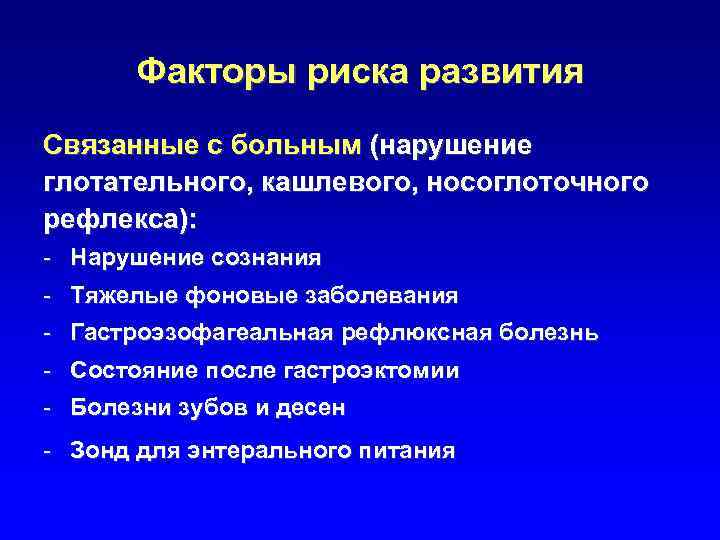

Факторы риска развития Связанные с больным (нарушение глотательного, кашлевого, носоглоточного рефлекса): - Нарушение сознания - Тяжелые фоновые заболевания - Гастроэзофагеальная рефлюксная болезнь - Состояние после гастроэктомии - Болезни зубов и десен - Зонд для энтерального питания